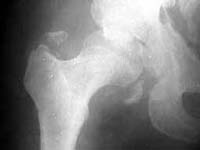

Seeking advice on management of 50 years old male who presented with infected fracture dislocation right hip with complete sciatic nerve palsy three months after injury. Xrays initial and current and CT scan Current images attached.

He was involved in a RTA about 3 months ago and underwent open reduction unsuccessfully followed by traction,elsewhere. The wound became infected. He came to me about a week ago in poor general condition with sinuses discharging pus. The sinus was explored. It led to the joint. The articular cartilage of both acetabulum and femoral head is completely destroyed. The posterior wall of the acetabulum was deficient and hip could not be reduced. Loose pieces from the joint were removed. Post op patient has been mobilised with frame. The sinus is slowly healing.

AP 3 mos ago

AP now

I am not certain why the hip is irreducible. The images show the femoral head completely posterior to the acetabulum with lots of bone fragments (presumably from posterior lip of acetabulum) anterior to the head nearly filling the acetabulum. You said bone fragments were removed. I would do whatever it took to reduce the head back into the socket.